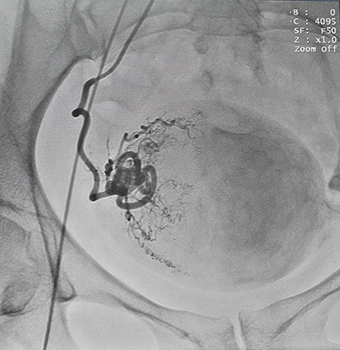

Эмболизация маточных артерий осуществляется рентген-хирургом в операционной,оснащенной ангиографической аппаратурой, под рентген-контролем. Доступом через бедренную или плечевую артерию при помощи специального катетера эмболизирующий препарат доставлен в артерии, питающие миому – последовательно справа и слева. Микроэмболы размером 500-700нм проникают в сосуды узла, блокируя их просвет, но в силу своих физических характеристик практически не попадают в сосуды, кровоснабжающие здоровые ткани. Питание тканей миомы прекращается, миома замещается соединительной тканью, уменьшается в размерах и как правило не требует дальнейшего лечения.

Кровоток в узле до ![]() |

и после процедуры эмболизации![]() |